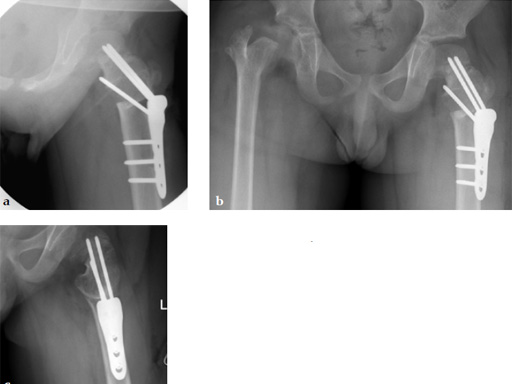

Case 2: LCP PHP 140. A 9-year-old boy, weighing 30 kg, had postinfectious pseudarthrosis of the femoral neck and varus deformity. His preoperative CC D angle was 80.

Case provided by Theddy Slongo, Bern, Switzerland